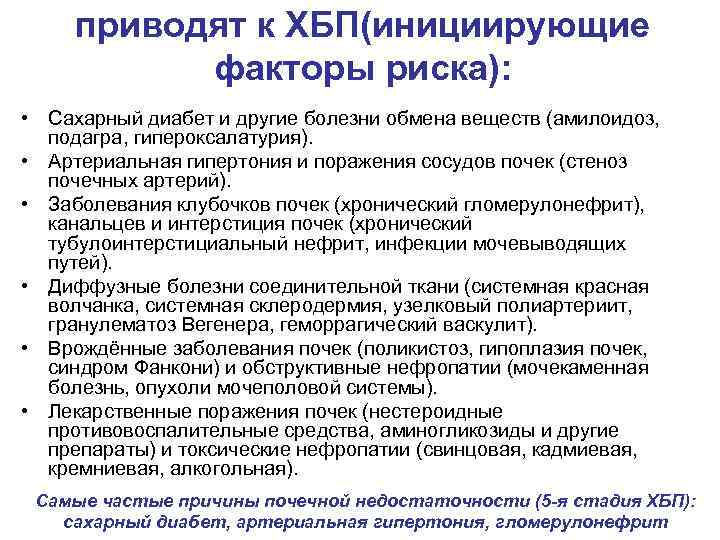

приводят к ХБП(инициирующие факторы риска): • Сахарный диабет и другие болезни обмена веществ (амилоидоз, подагра, гипероксалатурия). • Артериальная гипертония и поражения сосудов почек (стеноз почечных артерий). • Заболевания клубочков почек (хронический гломерулонефрит), канальцев и интерстиция почек (хронический тубулоинтерстициальный нефрит, инфекции мочевыводящих путей). • Диффузные болезни соединительной ткани (системная красная волчанка, системная склеродермия, узелковый полиартериит, гранулематоз Вегенера, геморрагический васкулит). • Врождённые заболевания почек (поликистоз, гипоплазия почек, синдром Фанкони) и обструктивные нефропатии (мочекаменная болезнь, опухоли мочеполовой системы). • Лекарственные поражения почек (нестероидные противовоспалительные средства, аминогликозиды и другие препараты) и токсические нефропатии (свинцовая, кадмиевая, кремниевая, алкогольная). Самые частые причины почечной недостаточности (5 -я стадия ХБП): сахарный диабет, артериальная гипертония, гломерулонефрит

приводят к ХБП(инициирующие факторы риска): • Сахарный диабет и другие болезни обмена веществ (амилоидоз, подагра, гипероксалатурия). • Артериальная гипертония и поражения сосудов почек (стеноз почечных артерий). • Заболевания клубочков почек (хронический гломерулонефрит), канальцев и интерстиция почек (хронический тубулоинтерстициальный нефрит, инфекции мочевыводящих путей). • Диффузные болезни соединительной ткани (системная красная волчанка, системная склеродермия, узелковый полиартериит, гранулематоз Вегенера, геморрагический васкулит). • Врождённые заболевания почек (поликистоз, гипоплазия почек, синдром Фанкони) и обструктивные нефропатии (мочекаменная болезнь, опухоли мочеполовой системы). • Лекарственные поражения почек (нестероидные противовоспалительные средства, аминогликозиды и другие препараты) и токсические нефропатии (свинцовая, кадмиевая, кремниевая, алкогольная). Самые частые причины почечной недостаточности (5 -я стадия ХБП): сахарный диабет, артериальная гипертония, гломерулонефрит